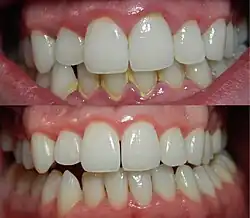

Prevention

Gingivitis can be prevented through regular oral hygiene that includes daily brushing and flossing.[13] Hydrogen peroxide, saline, alcohol or chlorhexidine mouth washes may also be employed. In a 2004 clinical study, the beneficial effect of hydrogen peroxide on gingivitis has been highlighted.[14] The use of oscillation type brushes might reduce the risk of gingivitis compared to manual brushing.[15]

Treatment

The focus of treatment is to remove plaque. Therapy is aimed at the reduction of oral bacteria and may take the form of regular periodic visits to a dental professional together with adequate oral hygiene home care. Thus, several of the methods used in the prevention of gingivitis can also be used for the treatment of manifest gingivitis, such as scaling, root planing, curettage, mouth washes containing chlorhexidine or hydrogen peroxide, and flossing. Interdental brushes also help remove any causative agents.